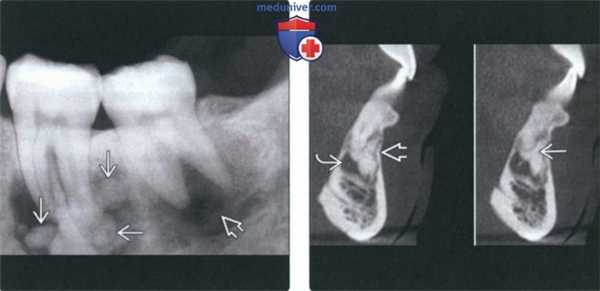

(Слева) На периапикальной рентгенограмме определяется склерозирующий остеит в области корней первого моляра нижней челюсти слева. Определяется также рарефицирующий остеит в области корней зуба. Обратите внимание на остеосклероз, «смешивающийся» с окружающей нормальной костью.

(Справа) На периапикальной рентгенограмме определяется хорошо отграниченное однородное затемнение с неровными краями у вершины первого моляра нижней челюсти справа. Пространства периодонтальной связки и твердые пластинки не изменены. (Слева) На периапикальных рентгенограммах нижних передних зубов определяется прогрессирующая периапикальная костная дисплазия. На рентгенограмме справа, выполненной через семь лет после левой, определяется постепенное нарастание минерализации очагов.

(Справа) На периапикальной рентгенограмме определяется луковицеобразное расширение кор ня с сохранением твердой пластинки и пространств ПДС, сопоставимое с гиперцементозом.

(Слева) На периапикальной рентгенограмме определяется ПКД в области вершин корней первого и второго моляров нижней челюсти. Затемнения в виде жемчужин представляют собой объемные образования цемента (промежуточная стадия ПКД). Очаг в области вершины второго моляра полностью рентгенонегативен (ранняя стадия ПКД).

(Справа) На КЛКТ (профильный срез) в области вершины корня центрального резца визуализируется включение цемента неправильной формы, напоминающее полумесяц. Обратите внимание на тонкое линейное просветление В речной стороны и истончение щечной и язычной кортикальных пла стинок. Наличие просветления позволяет предположить простую костную кисту.